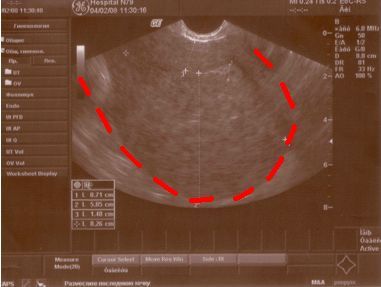

- УЗИ органов малого таза;

- Увеличение размера матки. При врастании эндометрия в миометрий матка женщины может приобретать шаровидную форму и достигать размеров, соответствующих нескольким месяцам беременности.